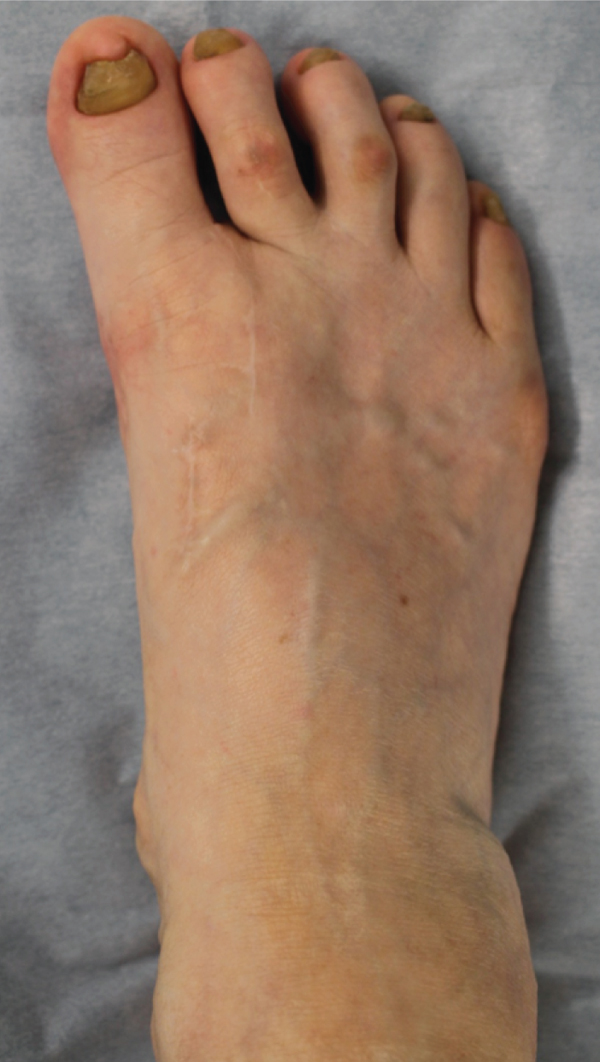

Her right foot exhibited a hallux varus deformity, and the second and third toes were dislocated dorsally (Figure 1(a)). Skin erosion at the dorsal aspect of the proximal interphalangeal joint of the second and third toes was observed. The range of motion (ROM) of the first MTP joint was 40° in dorsiflexion and 10° in plantarflexion. There was a tender callosity at the plantar aspect of the second metatarsal head. On plain radiographs, the hallux valgus angle was -24°, and the IMA was 0° (Figure 1(b)). The joint space at the first MTP joint was maintained.

(a)

(b)